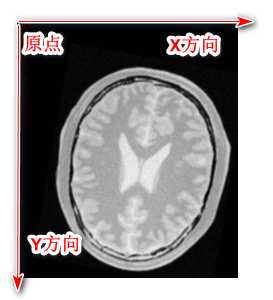

5- 我们的得到的图像,其原点位于左上方,水平方向为X轴,竖直方向为Y轴,如下:

验证如下:

在写校正之后的文件的时候,当我们把597行的平移参数设置为如下代码的时候:

//这里是用来验证图像的坐标轴的 centerMoving[0] = 40; centerMoving[1] = 40; centerFixed[0] = 0; centerFixed[1] = 0; initialTransform->SetTranslation(centerMoving - centerFixed); resample->SetTransform(initialTransform); //resample->SetTransform(registration->GetTransform());

我们得到的图像相比如原来的来说:

平移变大 原有图像

这个时候我们得到的图像相对于原来的来说,朝着左上角平移了一定距离。

所以上面猜想是正确的。